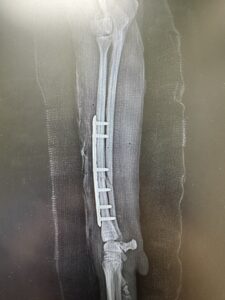

外科手術

• プレートやピンを使って骨を固定

• ずれが大きい場合や、治癒しにくい骨折では手術が選択されます